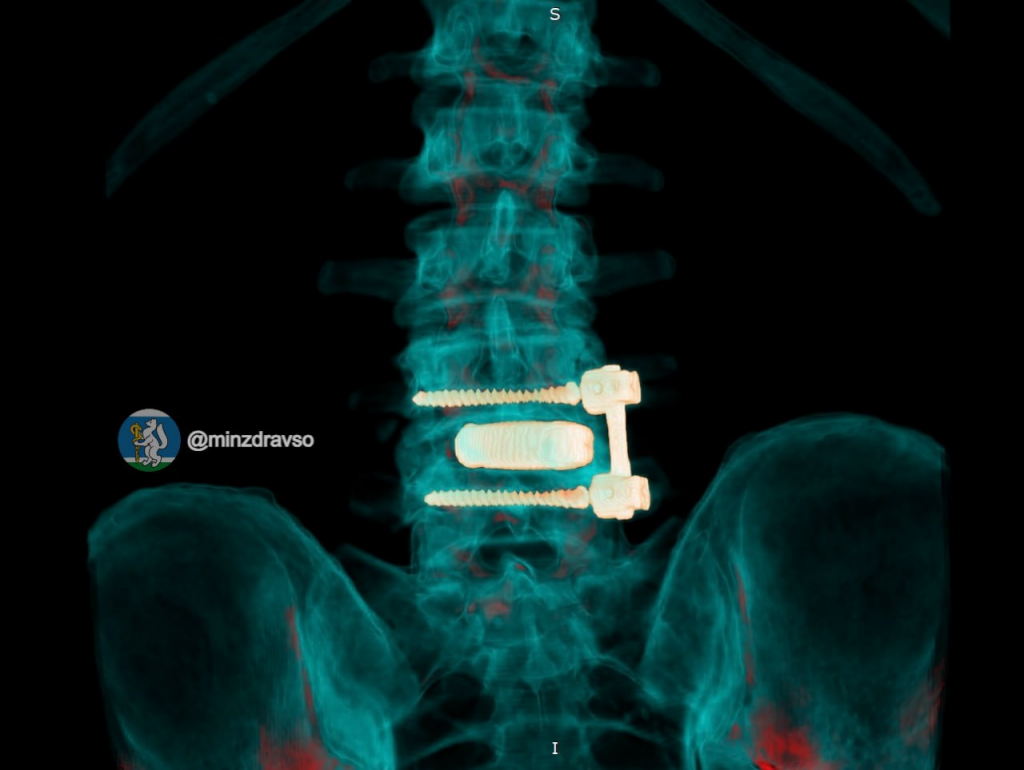

Пациенту имплантировали новую 3D-конструкцию, выполненную из титана по индивидуальным параметрам. Имплант зафиксировали отечественными спонгиозными винтами. Боль полностью прошла уже в первые сутки после операции: водитель скорой самостоятельно встал и начал ходить. Новый год он встретит в кругу семьи, а после реабилитации вернется на работу.